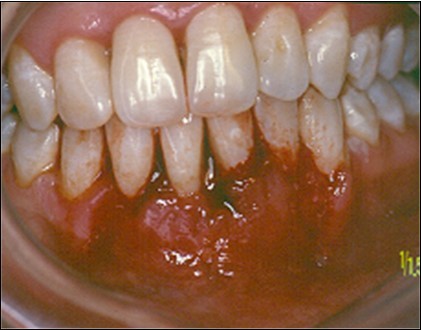

The patient under hard emotional stress that associated with bacterial plaque promoted ANUG with necrosis of alveolar bone and marginal gingival soft tissue in 31 and 41 (Figure 1). The patient was free of systemic disease and was not currently receiving any medication. Initial therapy was carried out using Er-YAG laser, to promote scaling and root planning and oral hygiene instruction. After initial therapy (Figure 2) the surgical method employed consists of the following steps as described by Langer and Langer5.

Figure 1.ANUG

ANUG